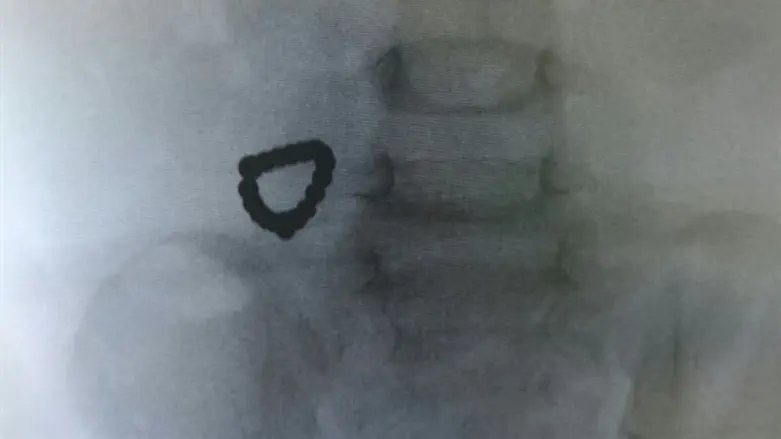

הילד הגיע ליחידה לרפואה דחופה (מיון) במרכז שניידר שהוא סובל מהקאות מרובות וכאבי בטן. בצילום הבטן שנעשה נראתה שרשרת, אך מכיוון שלא היה ידוע על בליעת המגנטים, ההנחה הייתה כי מדובר על שרשרת חרוזים.

בצילום בטן נוסף, נצפה כי "החרוזים" נשארו באותו המקום ולא נעו לכיוון היציאה מהגוף. אז עלה החשש כי מדובר במגנטים וקיים חשד לחסימת המעי. ולכן הייתה דחיפות בהוצאתם והילד הובהל לניתוח.

המגנטים שגרמו להתנקבות המעי הוצאו וצילום רנטגן נעשה על מנת לאשר כי כל המגנטים הוצאו. לאחר ההתאוששות מהניתוח ומההרדמה, עבר הפעוט להמשך טיפול והשגחה במחלקה הכירורגית.